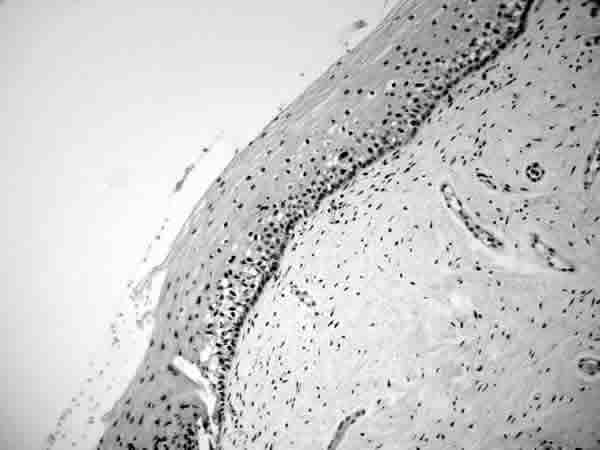

Fig. 3: Epitelio escamoso vaginal de estructura conservada con abundante pigmento en la zona basal (HE, 100x).